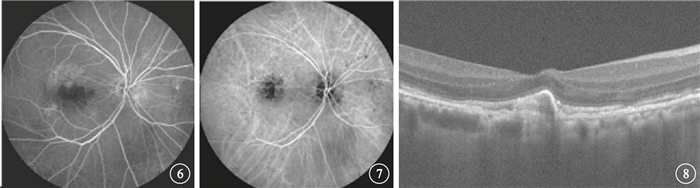

末次隨訪時,FFA、ICGA檢查發現,黃斑區CNV病灶滲漏消失(圖 6,7)6只眼,占30%;滲漏減輕11只眼,占55%;滲漏擴大3只眼,占15%。OCT檢查發現,所有患眼視網膜水腫消退,神經上皮脫離消失(圖 8),仍存在RPE脫離1只眼。

末次隨訪時,FFA、ICGA檢查發現,黃斑區CNV病灶滲漏消失(圖 6,7)6只眼,占30%;滲漏減輕11只眼,占55%;滲漏擴大3只眼,占15%。OCT檢查發現,所有患眼視網膜水腫消退,神經上皮脫離消失(圖 8),仍存在RPE脫離1只眼。